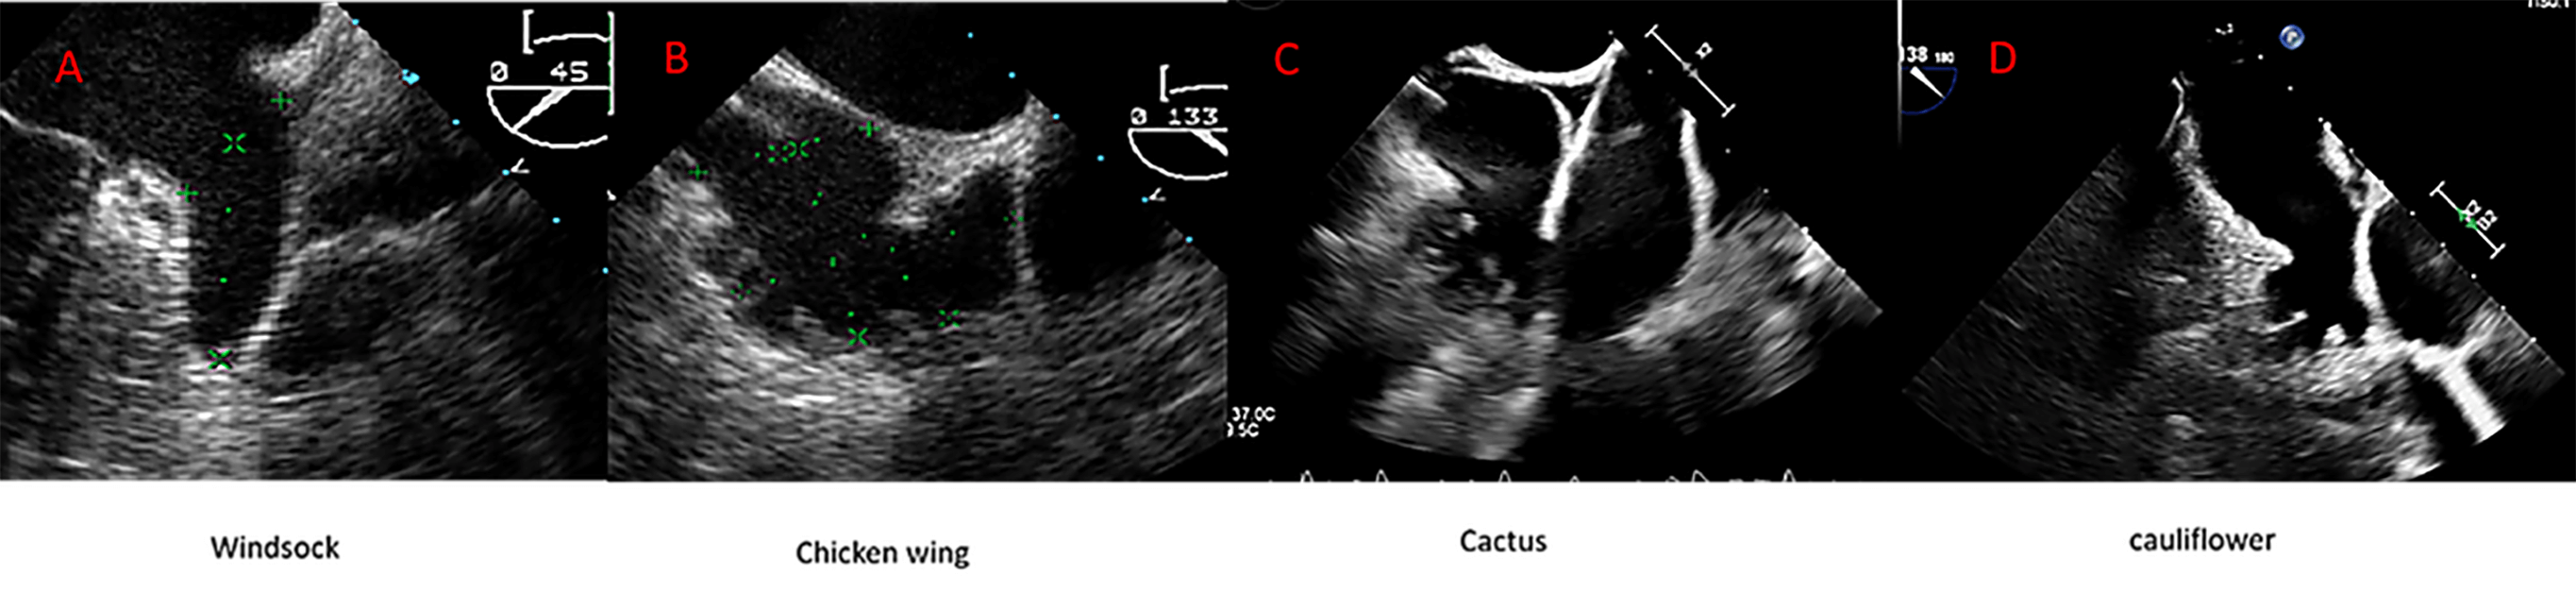

Fig. 4.

Left atrial appendage closure (LAAC) in a patient with complex anatomy. Transesophageal echocardiography (TEE) revealed a left atrial appendage (LAA) with a large proximal lobe, presenting a challenge for percutaneous closure. Nevertheless, an Amulet device was deployed successfully, with the lobe of the device positioned in the proximal lobe of the LAA and the disc effectively sealing the anatomical ostium.